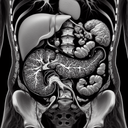

МРТ органів черевної порожнини

Магнітно-резонансна томографія (МРТ) органів черевної порожнини — це неінвазивний метод візуалізації, який використовує магнітне поле і радіохвилі для отримання детальних зображень внутрішніх органів та структур. Це дослідження допомагає лікарям виявляти й діагностувати різноманітні захворювання й патології, такі як пухлини, запальні процеси, камені в жовчному міхурі, ураження печінки та інші. Ось чому МРТ органів черевної порожнини важливе: 1...